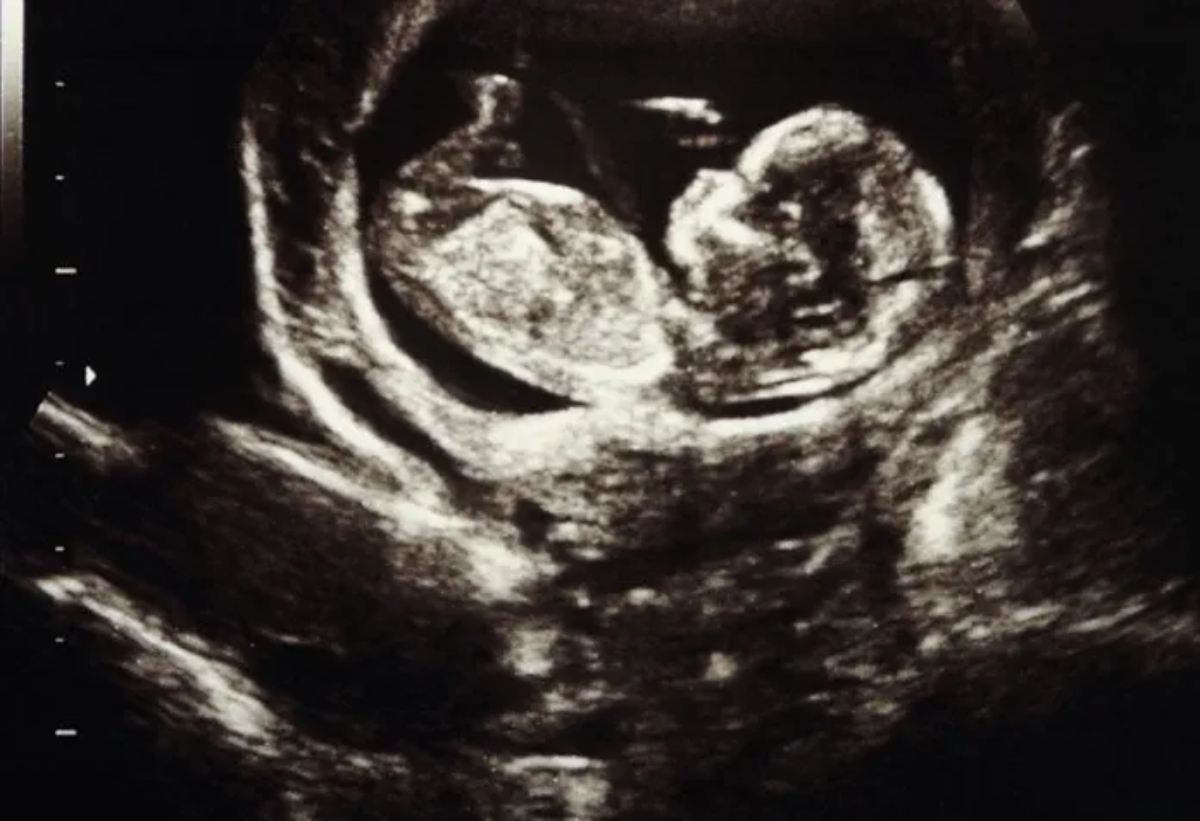

Χειρουργοί από τα Νοσοκομεία Παίδων και Brigham and Women’s της Βοστώνης πραγματοποίησαν μια πρωτοποριακή επέμβαση στον εγκέφαλο ενός εμβρύου 34 εβδομάδων, προκειμένου να διορθώσουν μια σπάνια προγεννητική πάθηση που ονομάζεται Δυσπλασία Φλέβας του Γαληνού (Vein of Galen Malformation).

Όπως αναφέρει το CNN, πρόκειται για μια πάθηση η οποία εμφανίζεται όταν το αιμοφόρο αγγείο που μεταφέρει αίμα από τον εγκέφαλο στην καρδιά, γνωστό και ως φλέβα του Γαληνού, δεν αναπτύσσεται σωστά. Αυτό έχει ως αποτέλεσμα την καταταπόνηση της φλέβας και της καρδιάς από την υπερβολική ποσότητα αίματος., που μπορεί να οδηγήσει σε μια σειρά προβλημάτων υγείας, όπως καρδιακή ανεπάρκεια. Μπορεί επίσης να προκαλέσει υπέρταση στις αρτηρίες των πνευμόνων και της καρδιάς, ενώ η επιπλέον πίεση στον εγκέφαλο μπορεί να προκαλέσει σημαντική εγκεφαλική βλάβη που οδηγεί σε νευρολογική και γνωστική εξασθένιση. Έχει επίσης υψηλό ποσοστό θνησιμότητας. Η επιτυχία της επέμβασης δίνει νέες ελπίδες για τη θεραπεία της πάθησης πριν κλιμακωθεί ο κίνδυνος επιπλοκών.